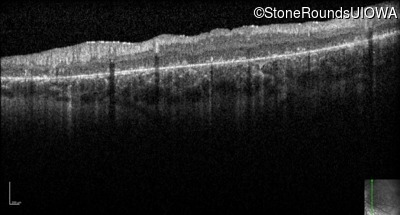

Optical Coherence Tomography - Right - 5/200

Exemplar / OCT Stack